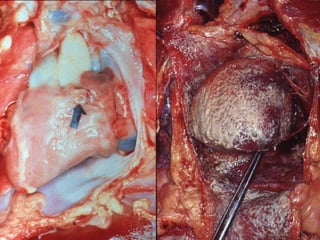

• Macroscopía: Engrosamiento fibroso de la pared del cayado

aórtico con estrechamiento y oclusión de las bocas de origen de

los vasos que nacen del mismo